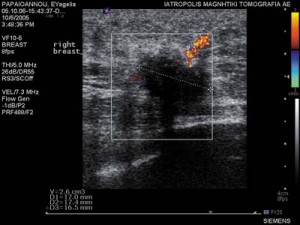

Οι Υπέρηχοι υψηλής ευκρίνειας είναι μέθοδος που δεν χρησιμοποιεί ακτινοβολία και επιτρέπει στα χέρια έμπειρου απεικονιστή να λύσει προβλήματα που αφορούν:

H Υπερηχητική Μαστογραφία είναι η εξέταση εκλογής σε νεαρές γυναίκες μικρότερες των 30 ετών και αποτελούν συμπληρωματική εξέταση σε γυναίκες με πυκνούς μαστογραφικά μαστούς.

H Υπερηχητική Μαστογραφία είναι η εξέταση εκλογής σε νεαρές γυναίκες μικρότερες των 30 ετών και αποτελούν συμπληρωματική εξέταση σε γυναίκες με πυκνούς μαστογραφικά μαστούς.

Κατευθύνουν με ακρίβεια βιοψίες βλαβών που απεικονίζονται υπερηχοτομογραφικά.